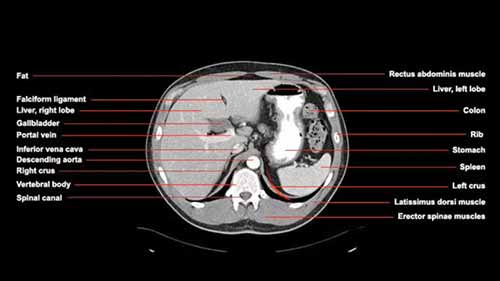

放射学和计算机断层扫描

本期课程涵盖了放射学的历史、X射线原理、CT窗位、CT造影等内容。